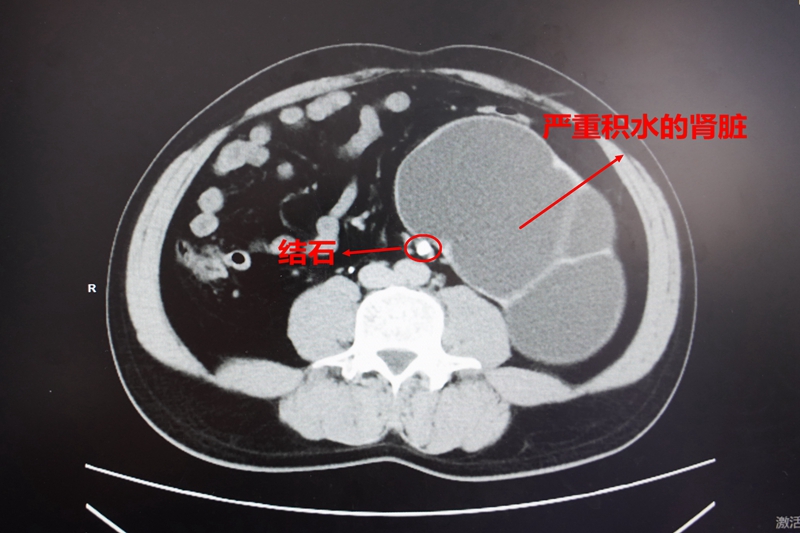

检查结果让所有人倒吸一口凉气:张姨的右肾已重度积水,原本饱满的肾脏像被长期吹胀的气球,彻底失去弹性,肾功能已不可逆地完全丧失。

而这场悲剧的元凶,竟是一枚卡在输尿管上段的陈旧性结石残骸! 医生高度怀疑,这正是十年前碎石术后未排出、也未被察觉的 “漏网之石”,在体内悄悄长大,最终酿成大祸。